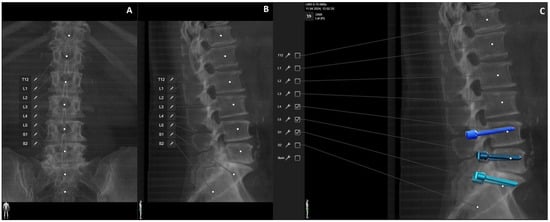

Figure 9. Same patient as in Figure 1, Figure 2 and Figure 7. (A) iCT scan with AI-assisted vertebra recognition. (B) Screw trajectory in the preoperative CT. (C) iCT scan after fusion with preoperative CT shows the screw trajectories, with the option of correcting the screw planning according to the iCT scan.